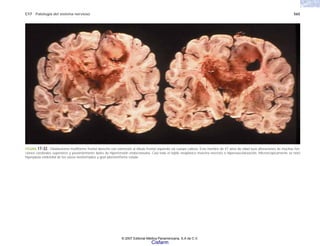

LA PATOLOGÍA EN LOS ALBORES

distintas formas, por ejemplo fiebre, vómitos de sangre,